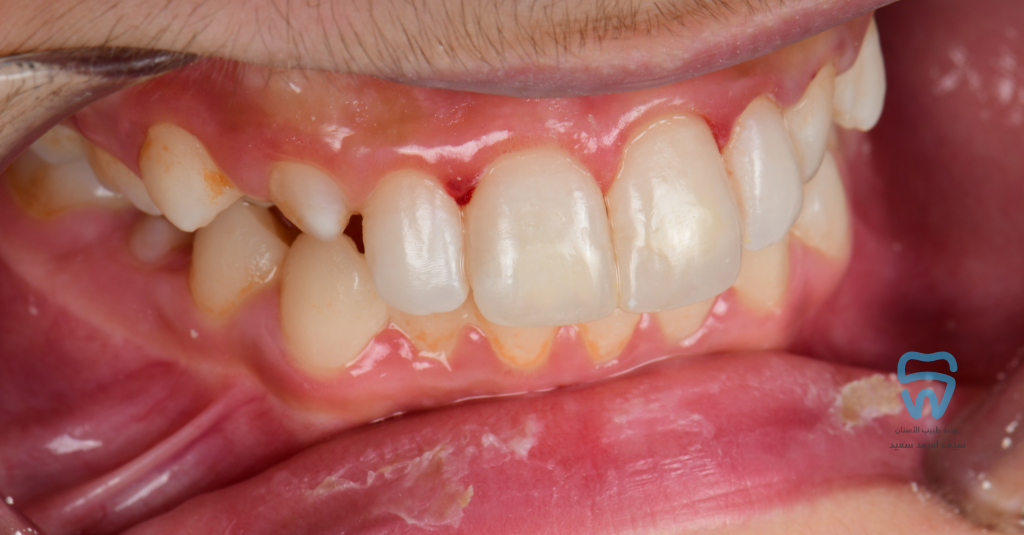

Finished and polished

1 year follow-up